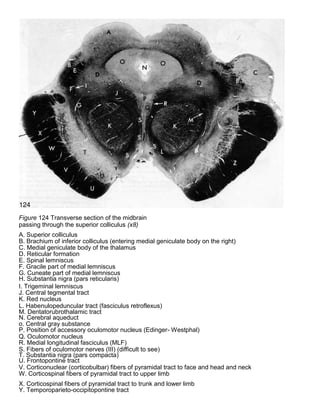

Figure 124 Transverse section of the midbrain

passing through the superior colliculus (x8)

A. Superior colliculus

B. Brachium of inferior colliculus (entering medial geniculate body on the right)

C. Medial geniculate body of the thalamus

D. Reticular formation

E. Spinal lemniscus

F. Gracile part of medial lemniscus

G. Cuneate part of medial lemniscus

H. Substantia nigra (pars reticularis)

I. Trigeminal lemniscus

J. Central tegmental tract

K. Red nucleus

L. Habenulopeduncular tract (fasciculus retroflexus)

M. Dentatorubrothalamic tract

N. Cerebral aqueduct

o. Central gray substance

P. Position of accessory oculomotor nucleus (Edinger- Westphal)

Q. Oculomotor nucleus

R. Medial longitudinal fasciculus (MLF)

S. Fibers of oculomotor nerves (III) (difficult to see)

T. Substantia nigra (pars compacta)

U. Frontopontine tract

V. Corticonuclear (corticobulbar) fibers of pyramidal tract to face and head and neck

W. Corticospinal fibers of pyramidal tract to upper limb

X. Corticospinal fibers of pyramidal tract to trunk and lower limb

Y. Temporoparieto-occipitopontine tract

Z. Crus cerebri

Figure 124 Transversesection of the midbrain passing through the superior colliculus (x8) A. Superior colliculus B. Brachium of inferior colliculus (entering medial geniculate body on the right) C. Medial geniculate body of the thalamus D. Reticular formation E. Spinal lemniscus F. Gracile part of medial lemniscus G. Cuneate part of medial lemniscus H. Substantia nigra (pars reticularis) I. Trigeminal lemniscus J. Central tegmental tract K. Red nucleus L. Habenulopeduncular tract (fasciculus retroflexus) M. Dentatorubrothalamic tract N. Cerebral aqueduct o. Central gray substance P. Position of accessory oculomotor nucleus (Edinger- Westphal) Q. Oculomotor nucleus R. Medial longitudinal fasciculus (MLF) S. Fibers of oculomotor nerves (III) (difficult to see) T. Substantia nigra (pars compacta) U. Frontopontine tract V. Corticonuclear (corticobulbar) fibers of pyramidal tract to face and head and neck W. Corticospinal fibers of pyramidal tract to upper limb X. Corticospinal fibers of pyramidal tract to trunk and lower limb Y. Temporoparieto-occipitopontine tract